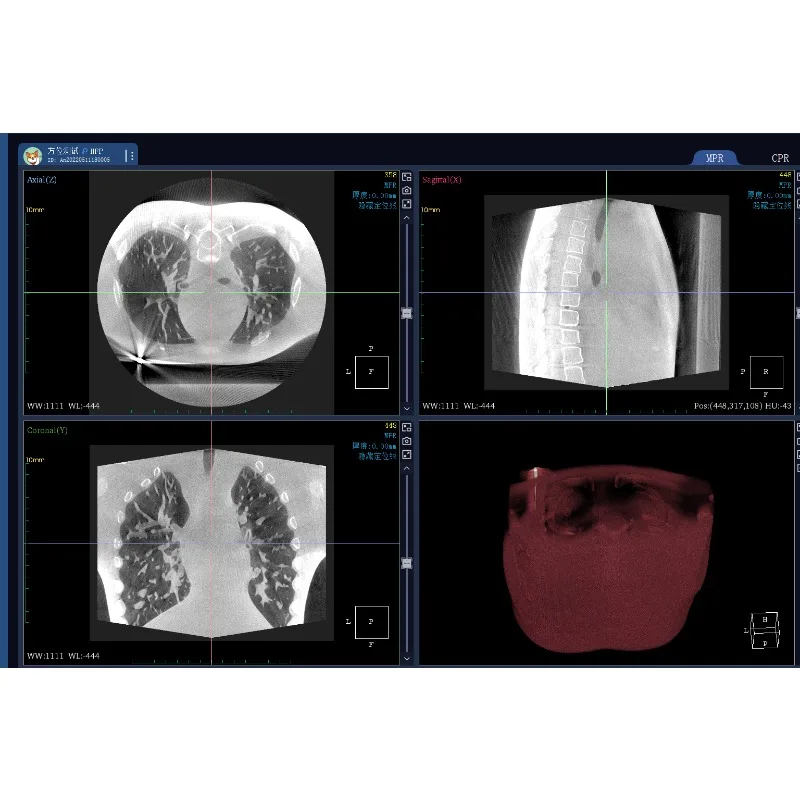

Exclusive Scanning and lmaging System

For High-resolution lmages

Dynamic Range Pixel Array Detector

Amorphous Silicon Cesium lodide

Active area: 25 cm x 30 cm, pixel pitch: 120 um

Lossless image reconstruction: Large-angle cone beam, true isotropic voxel

(identical length, width and height), and zero loss of axial image details

A slice thickness of 0.24 mm, high spatial resolution, and rich details